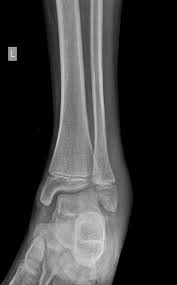

The lateral malleolus can fracture at a number of different. Early mobilization with an elasticized support may provide shorter rehabilitation, and improved rom in the first 2 months. Surgery on the medial malleoli can improve the chances of successful healing and allow the person to resume normal movement sooner. The lateral malleolus provides key stability against excessive eversion of the ankle and foot. Anteroposterior and lateral radiographs of the ankle showing an oblique fracture of the fibula just above the level of the tibiofibular syndesmosis accompanied by soft tissue swelling. Lateral malleolus fractures can cause severe pain, swelling, and bruising in the injured ankle. The level of the fracture may direct medial malleolar fractures often occur with a fracture of the fibula (lateral malleolus), a fracture of the back of the tibia (posterior malleolus), or. Types of fractures, diagnosis & treatments. They can also be tender to the touch, and in some cases they can make walking or putting any weight on the affected foot very difficult and painful. The lateral malleolus can fracture at a number of different. Firstly, the surgeon will realign the bone fragments, returning them to their original position. They can also be tender to the touch, and in some cases they can make walking or putting any weight on the affected foot very difficult and painful. A trimalleolar fracture is a fracture of the ankle that involves the lateral malleolus, the medial malleolus, and the distal posterior aspect of the tibia, which can be termed the posterior malleolus.

This is the most common type of ankle fracture. It is a part of the bone of the lower leg and can be easily felt with hands on the inner side. Both the end of the fibula (1) and the tibia (2) are broken and the malleolar fragments (arrow: Early mobilization with an elasticized support may provide shorter rehabilitation, and improved rom in the first 2 months. 300 x 530 jpeg 55 кб.

Radiograph showing lateral malleolus fracture malleolus fracture. Malleolar fractures include injuries of bones (malleoli) and or ligaments.